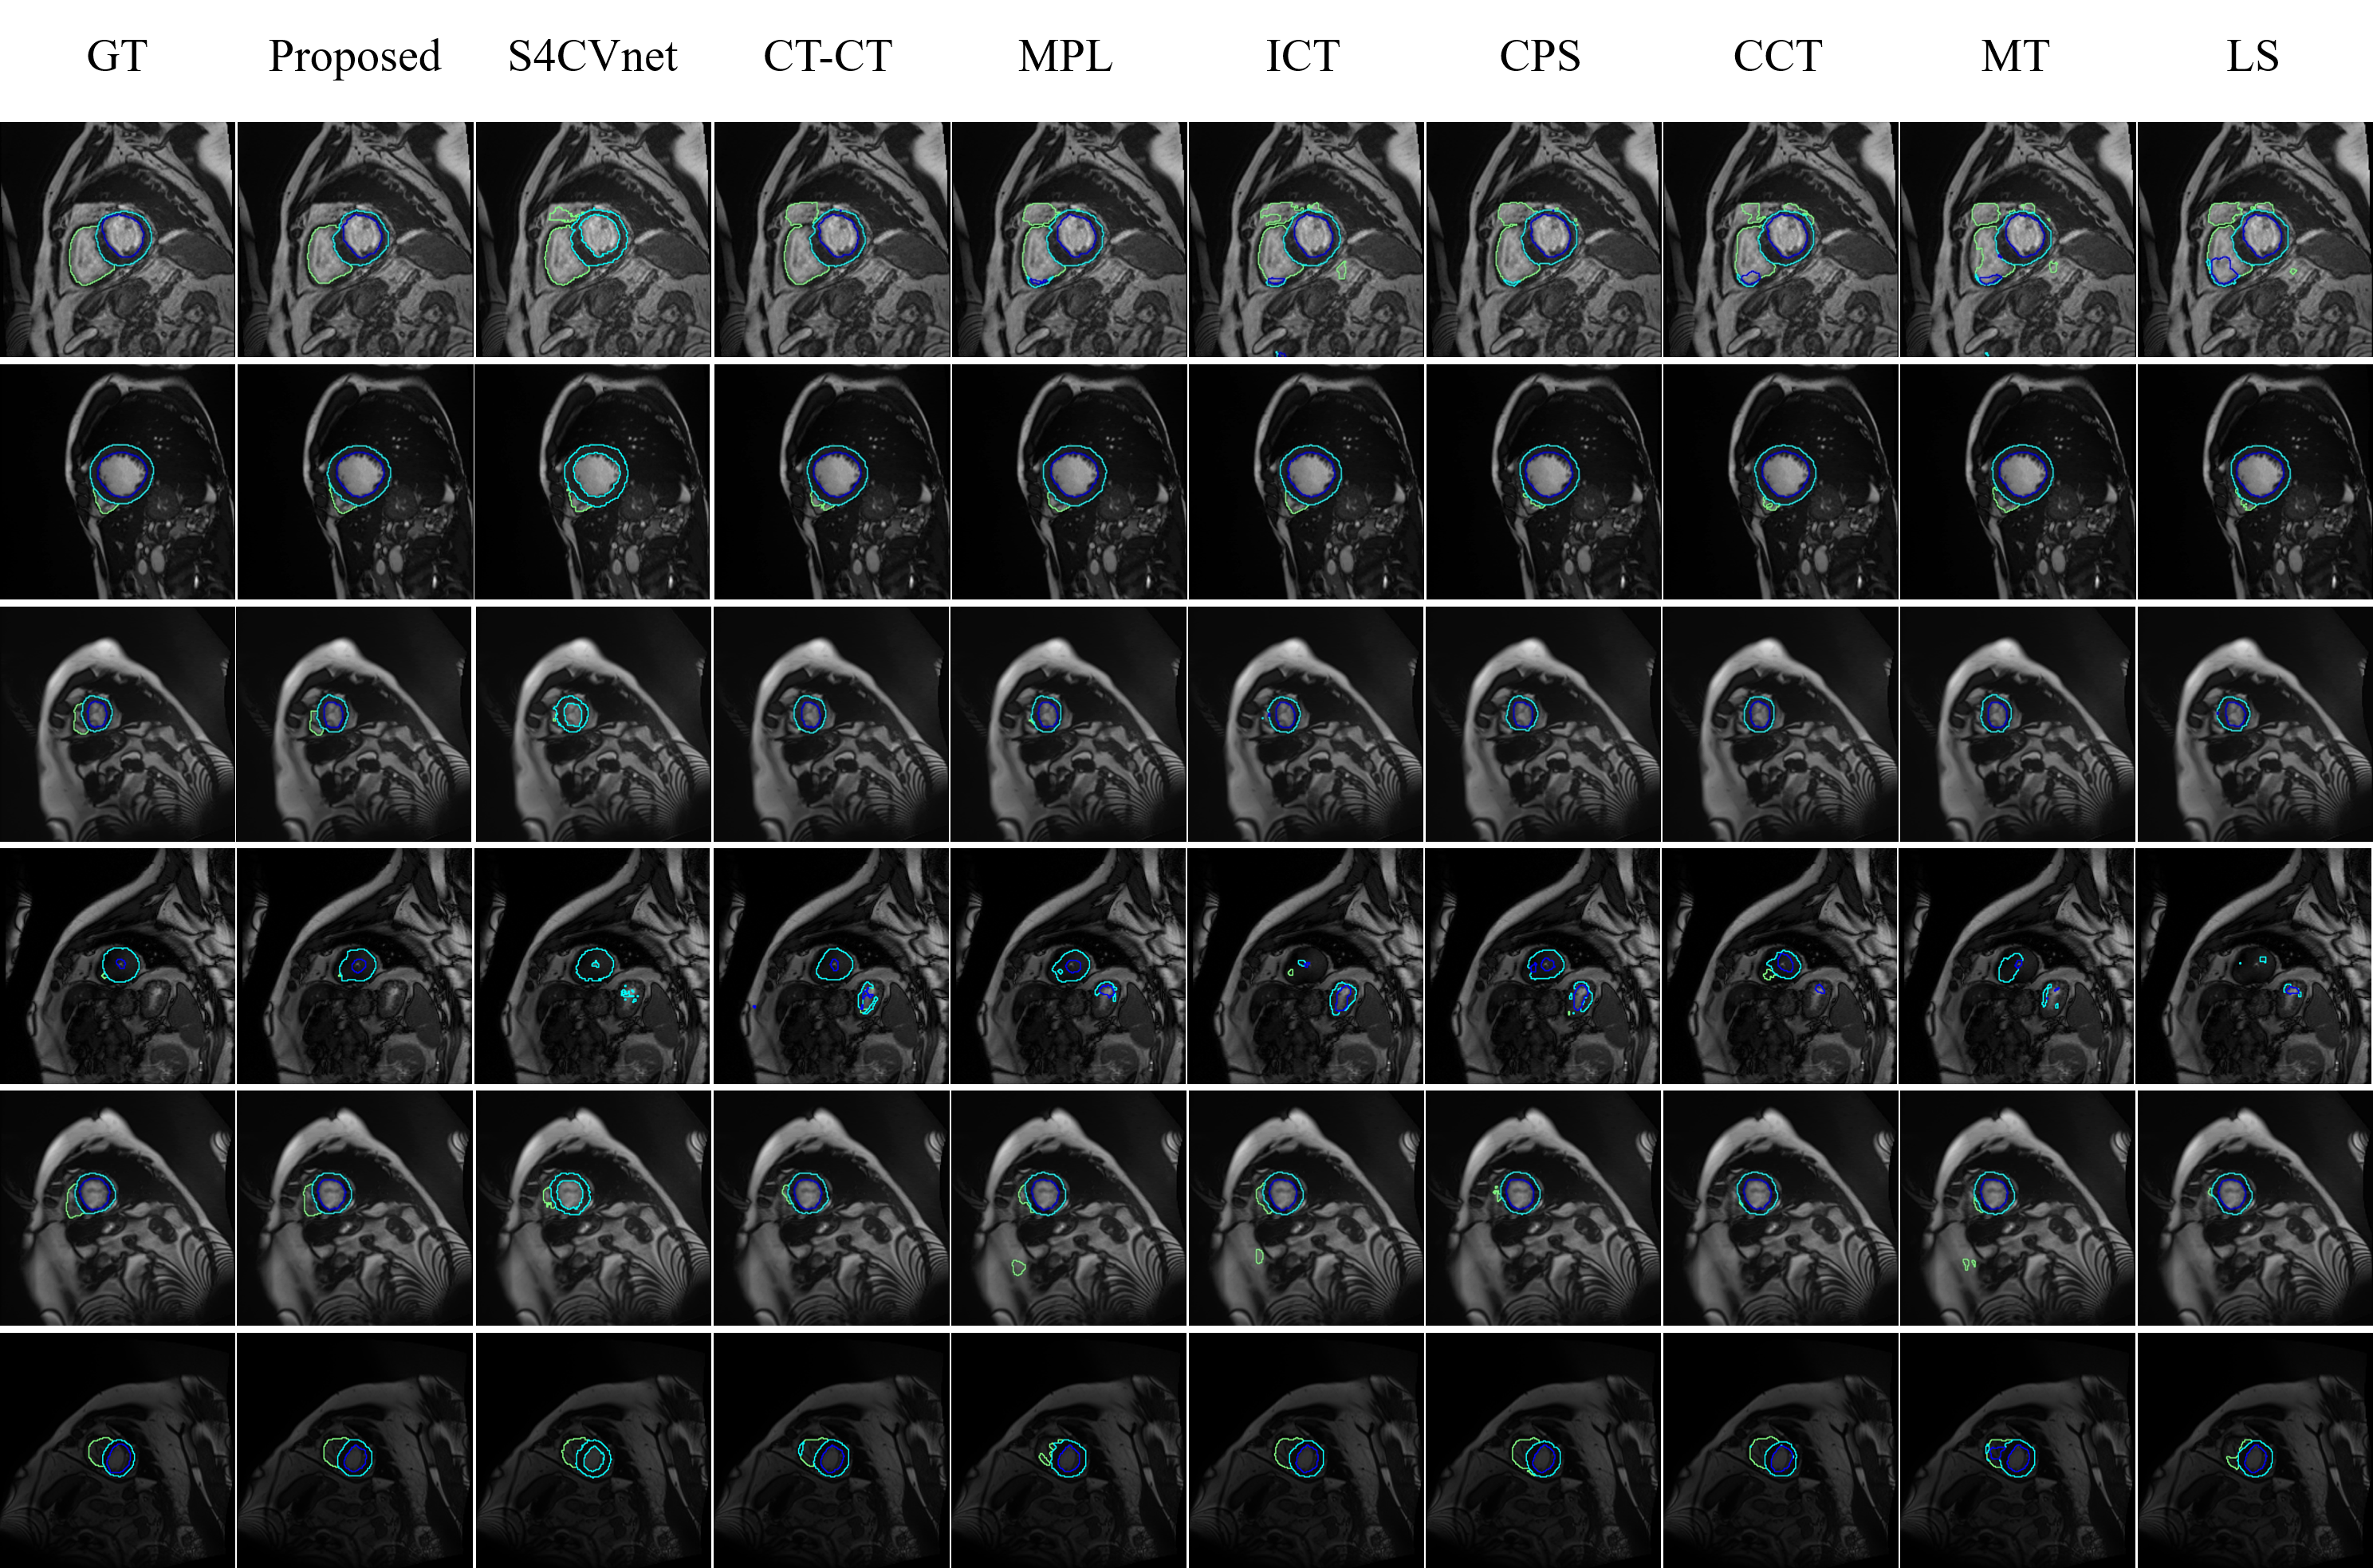

Figure 6: Examples of segmentation results for the ACDC dataset with 10% labeled training examples. From left to right: Ground Truth (GT), the proposed framework, S4CVnet[42], Cross Teaching between CNN Transformers[31] (CT-CT), Meta Pseudo Label (MPL)[33], Interpolation Consistency Training[39] (ICT), Cross Pseudo Supervision[10] (CPS), Cross Consistency Training[31] (CCT), Mean Teacher[38] (MT), and Limited Supervised (LS) Learning.

Figure 6 visually contrasts the segmentation results of different semi-supervised frameworks, using 7 labeled cases for training. Our method outperforms S4CVnet by achieving more intact object segmentations. In particular, our approach excels in the accurate segmentation of right ventricles, closely resembling the ground truth. In addition, our method has fewer false positive regions, highlighting its accuracy.